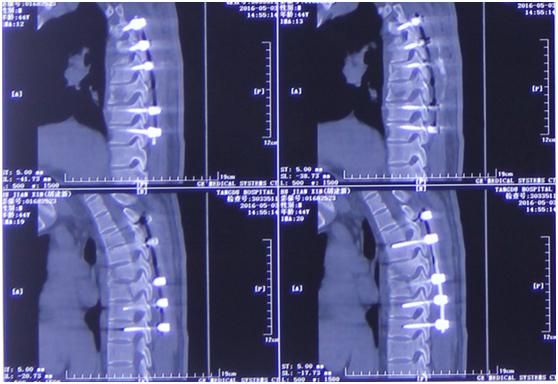

随后,李维新教授紧急对患者行“全麻下后中正肌间隙入路胸椎体爆裂性骨折复位神经减压植骨融合内固定术”。术后,王先生症状缓解明显,约两周后即出院调养。

影像学资料

手术前后对比

“我们通过脊间隙制钉把脊柱完全复位了,而且对这个脊髓进行了一期的减压,减除脊髓致压物,很大程度保留脊髓功能。”李维新教授回忆“术中我们看到脊髓搏动是恢复的,而且患者脊髓复位也非常好。”